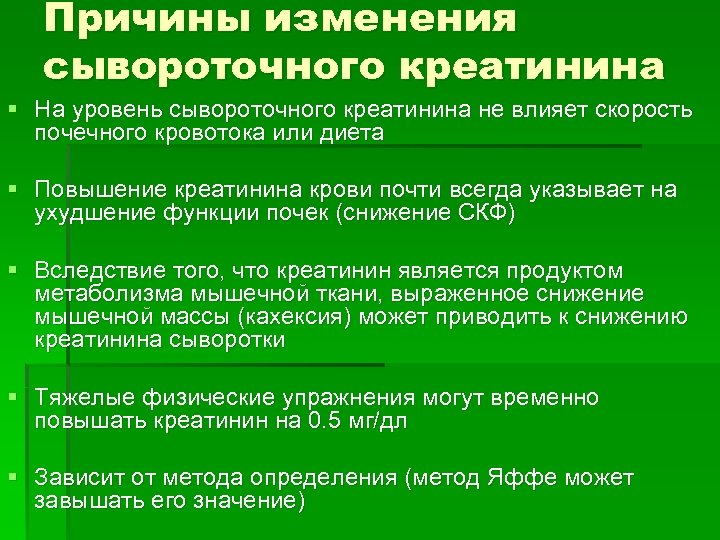

Причины изменения сывороточного креатинина § На уровень сывороточного креатинина не влияет скорость почечного кровотока или диета § Повышение креатинина крови почти всегда указывает на ухудшение функции почек (снижение СКФ) § Вследствие того, что креатинин является продуктом метаболизма мышечной ткани, выраженное снижение мышечной массы (кахексия) может приводить к снижению креатинина сыворотки § Тяжелые физические упражнения могут временно повышать креатинин на 0. 5 мг/дл § Зависит от метода определения (метод Яффе может завышать его значение)